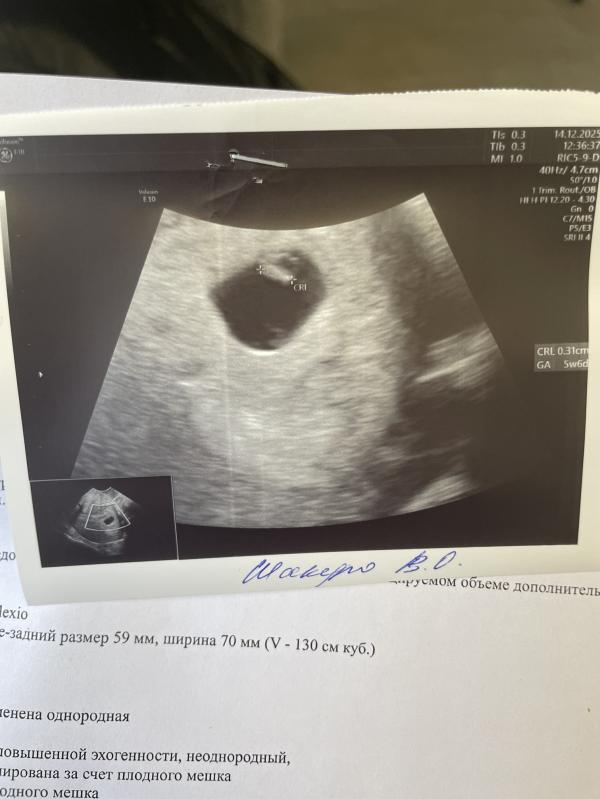

Ии пишет, что отсутствуе сердцебиения при ктр 7 это тревожный признак.

По узи срок 5-6 недель. Через неделю будет сердцебиение

Если написано, что КТР на срок 5,6 недель, то сам плод развился именно на этот «возраст», значит еще неделя в запасе есть, чтобы сердцебиение появилось. Не переживайте, пусть все будет хорошо. Еще можно было бы по ХГЧ отследить развивается ли по норме беременность, но после какого-то срока уже не показательно оно. Поэтому лучше переделать узи чуть позже и прислушивайтесь к ощущениям, если боль или кровотечение, сразу скорую, если все спокойно - наблюдайте пока.

Ну я записалась на через неделю-жду,но она меня немного расстроила,что при таком КТР уже должно быть СБ

Если всё хорошо, то буквально со дня на день уже сердечко должно застучать. При условии что аппарат узи хороший . Посмотрела свое узи-3,3 мм -сб +